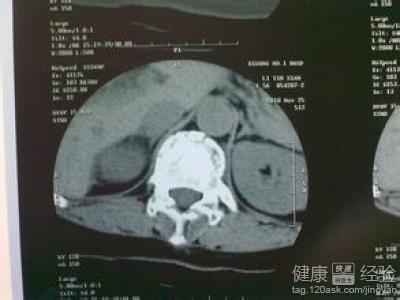

肌張力是指肌肉在靜止和松弛狀態下的緊張度。肌張力高的話會在運動和靜止時都會表現出來異常的姿勢。人體的肌張力是維持人體本身各種姿勢以及正常運動的基礎。一般肌張力高和大腦損傷有關系,所以建議你還是先去醫院給孩子做個腦部的檢查。若是比較輕的話做按摩和被動操過段時間會好的。若是程度嚴重,做父母的也不要手足無措,選擇科學的方法,肌張力高是有治愈希望的。

1肌張力是指肌肉在靜止和松弛狀態下的緊張度,它是維持人體本身各種姿勢以及正常運動的基礎。一般肌張力高和大腦損傷有關系,先去醫院給孩子檢查下腦部吧。如果真的是有損傷,咱們也能早發現早治療啊。

2肌張力高的話會在運動和靜止時都會表現出來異常的姿勢。看病時可不要隱瞞大夫,像懷孕時胎兒情況怎麼樣,是不是有過什麼對胎兒不利的事,孩子是不是早產,出生時具體情況什麼的都要說出來,這樣有利於大夫確診和治療。

3肌張力高也是有輕有重。若是情況嚴重就聽大夫的吃藥打針及時治療,要是輕微的,父母可以學學寶寶撫觸,再給寶寶做做被動操。大腦在頭六個月發育最快,可塑性最強,千萬別錯過了這個康復的最佳時間段。